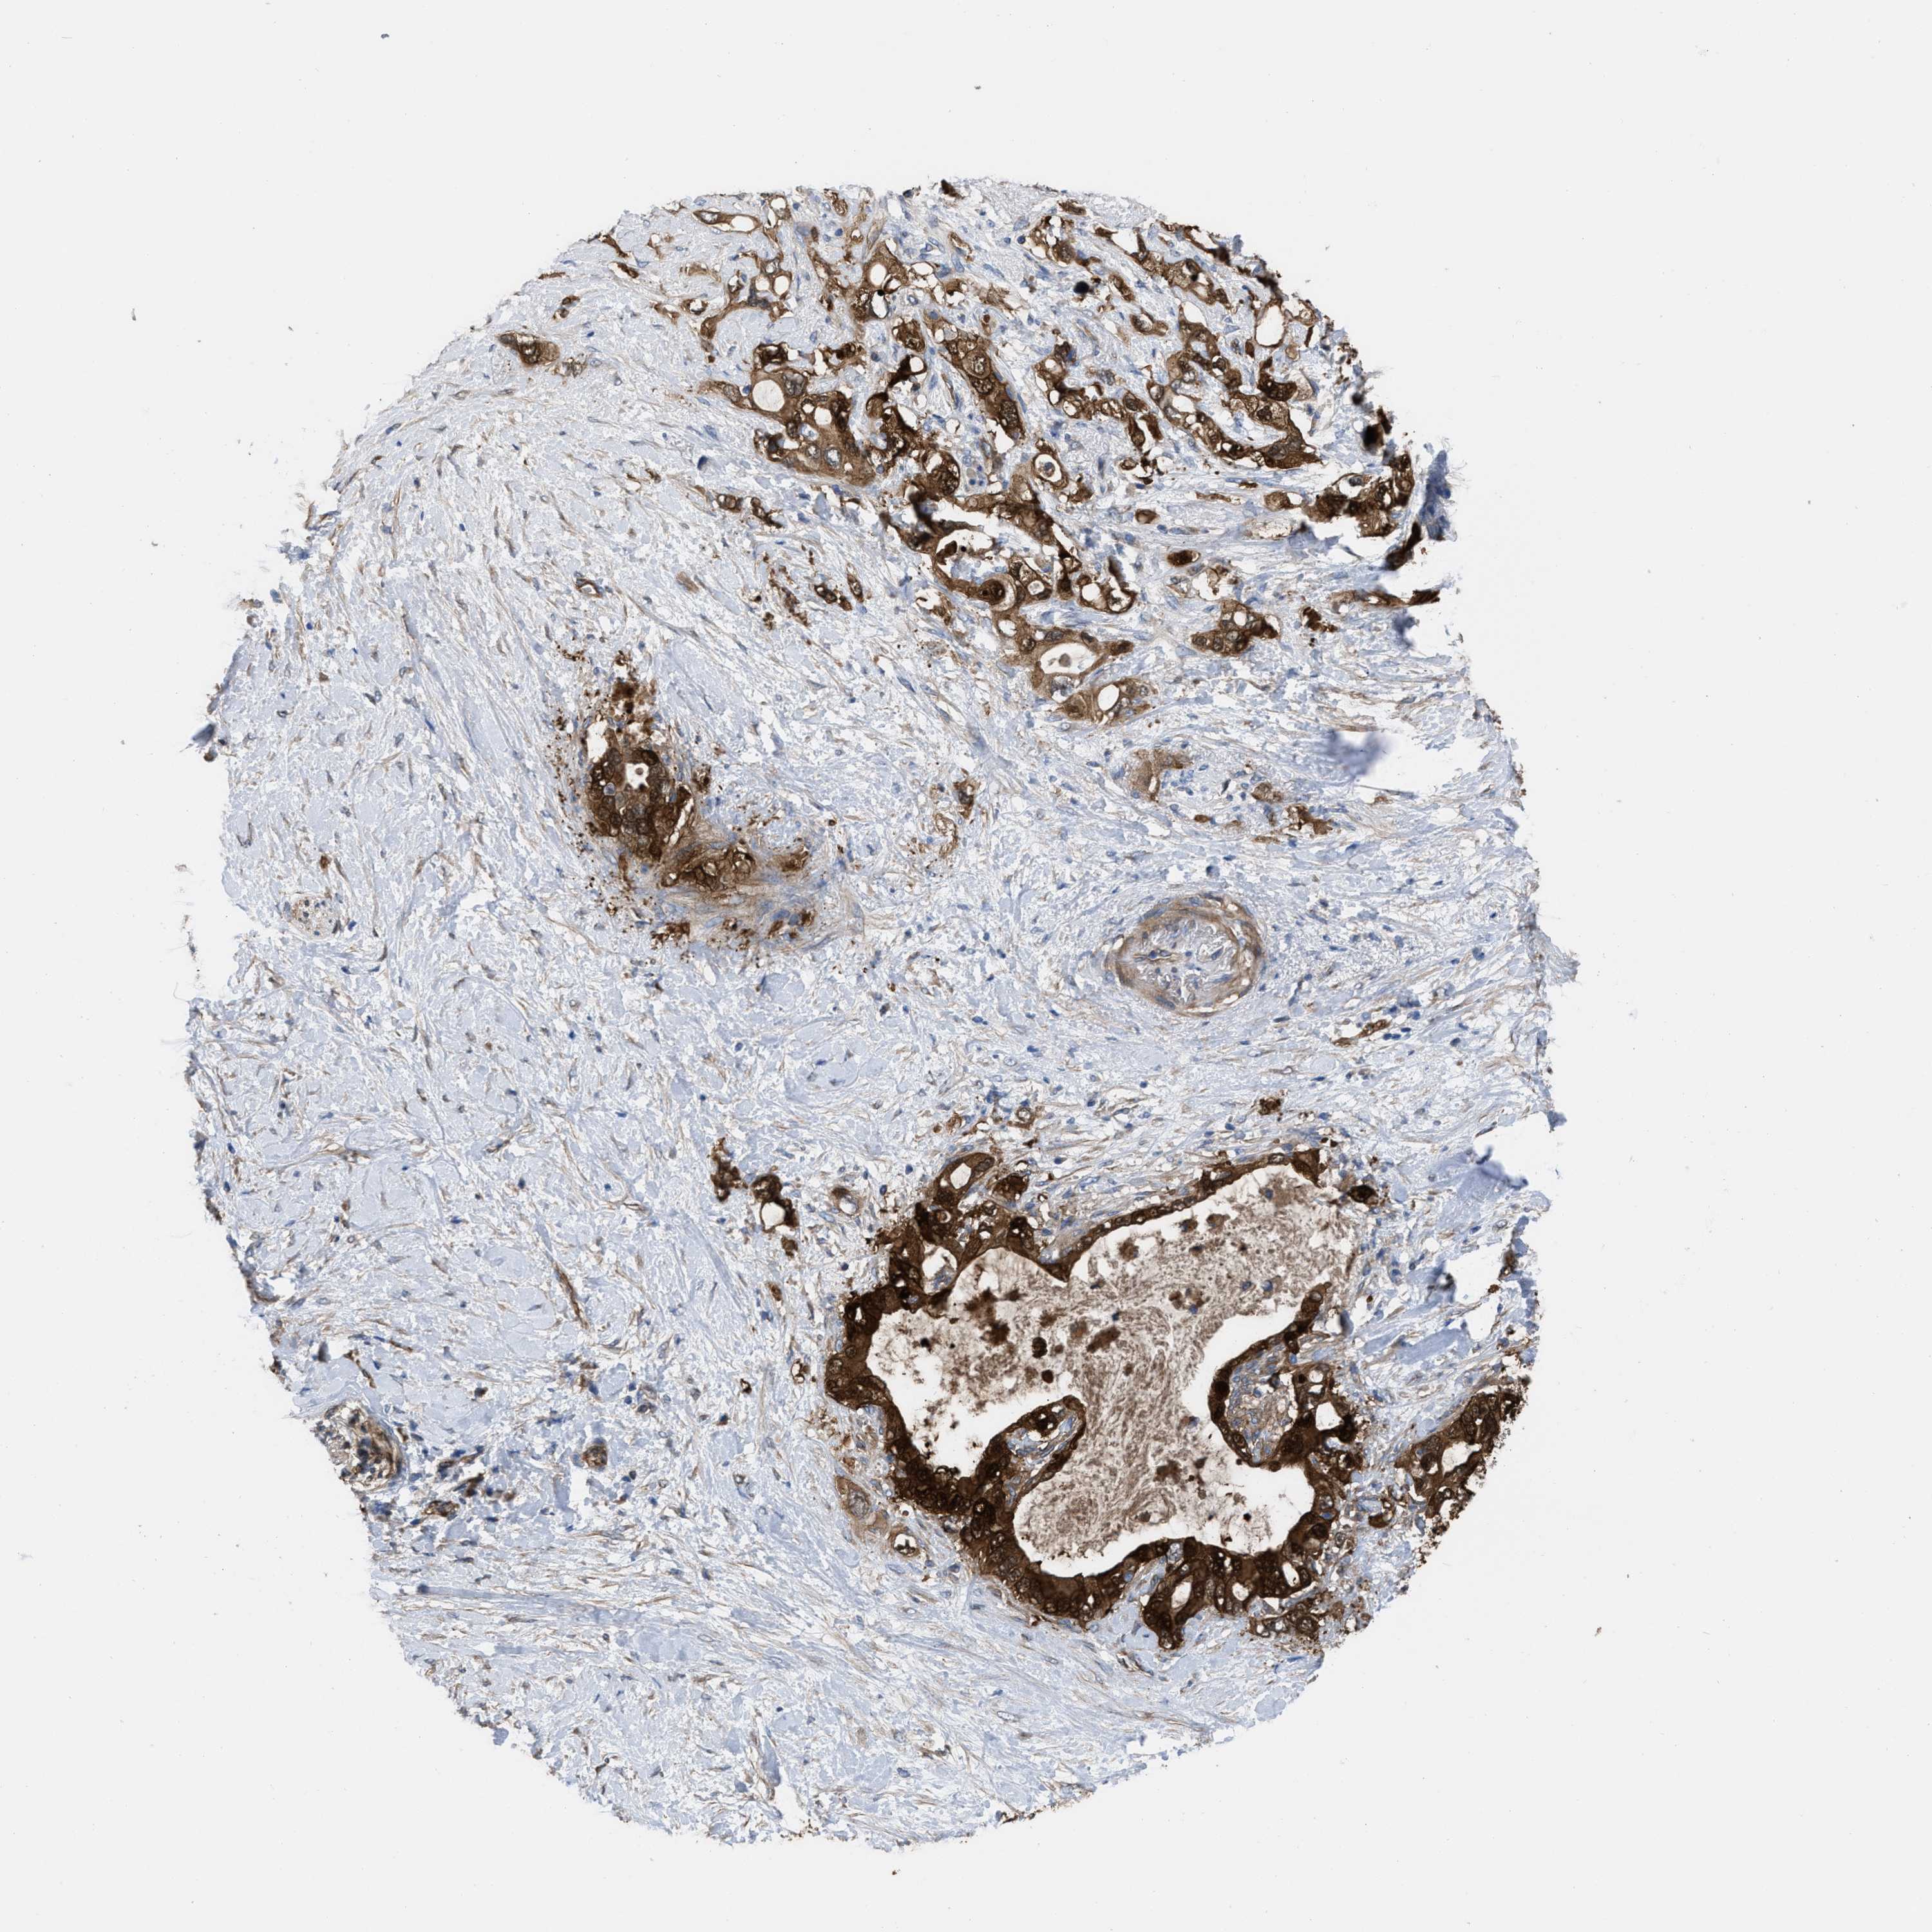

PANCREATIC CANCER - Protein expressioni

A mouse-over function shows sample information and annotation data. Click on an image to view it in a full screen mode. Samples can be filtered based on level of antibody staining by selecting one or several of the following categories: high, medium, low and not detected. The assay and annotation is described here.

Note that samples used for immunohistochemistry by the Human Protein Atlas do not correspond to samples in the TCGA dataset.

Antibody stainingi

Antibody staining in the annotated cell types in the current human tissue is reported as not detected, low, medium, or high, based on conventional immunohistochemistry profiling in selected tissues. This score is based on the combination of the staining intensity and fraction of stained cells.

Each image is clickable and will lead to virtual microscopy that enables deeper exploration of all samples and also displays staining intensity scores, fraction scores and subcellular localization as well as patient and tissue information for each sample.

Antibody HPA003747

Antibody HPA019769

Staining

High

Medium

Low

Not detected

Intensity

Strong

Moderate

Weak

Negative

Quantity

>75%

75%-25%

<25%

None

Location

Nuclear

Cytoplasmic/membranous

Cytoplasmic/membranous,nuclear

Adenocarcinoma, NOS

Adenocarcinoma, metastatic, NOS